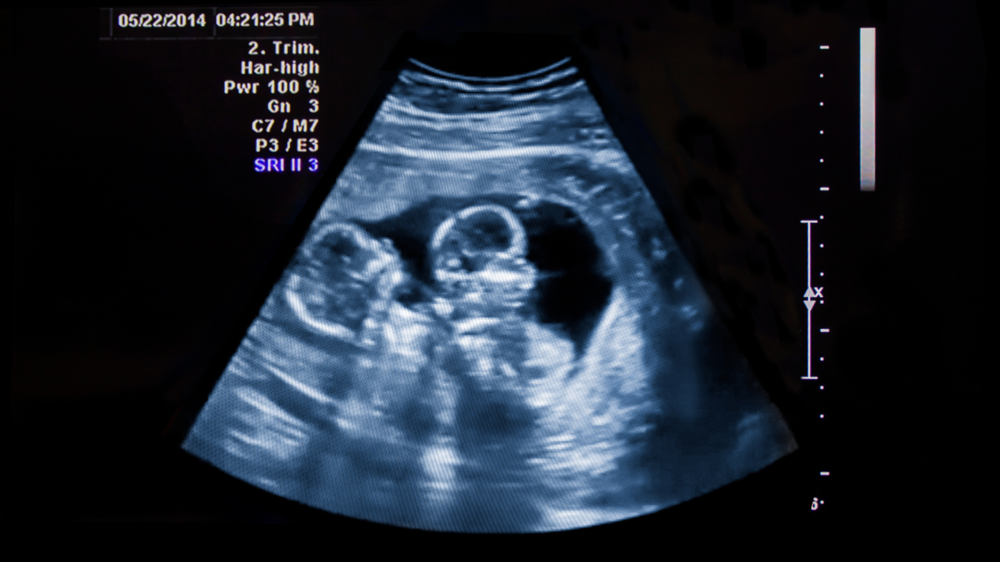

twin pregnancy

When you have twins, every kick, flutter, or roll is a small sense of reassurance. However, you may notice one twin moves much more than the other. You may wonder if this is normal or something to be concerned about. Note that differences in foetal activity between twins are common and do not necessarily mean there is a reason to worry.